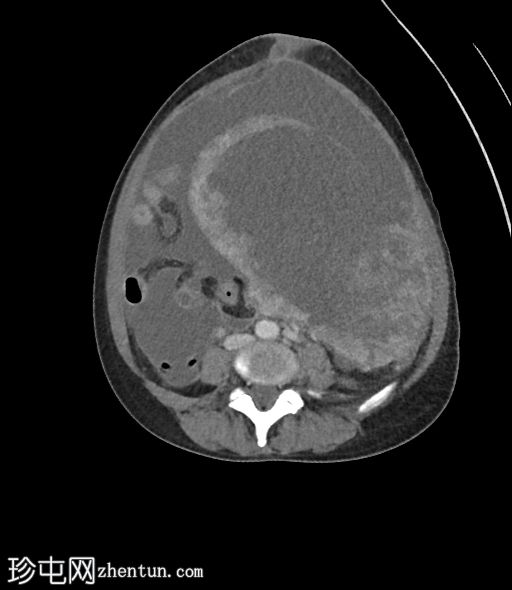

6个月前MRI检查

MRI

轴位

T2加权像

3.jpg

与既往CT同时进行的MRI检查显示子宫内有多发性T2低信号强度肌瘤,但在子宫右侧一个肌瘤内可见一处不均匀、中心高T2/囊性信号区。